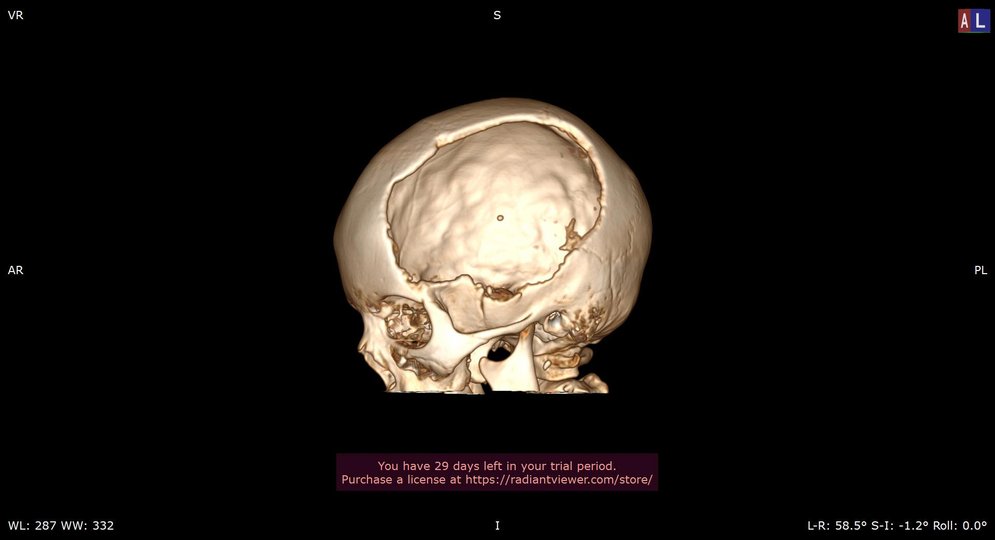

“У центрі ортопедичних стін – Траума, у нашій лікарні було проведено ряд складних хірургічних втручань, 28 січня – видалення внутрішньочерепної гематоми, череп декомпресії та 13 березня – череп з встановленням титанової пластини”– – сказав він у медичній установі.